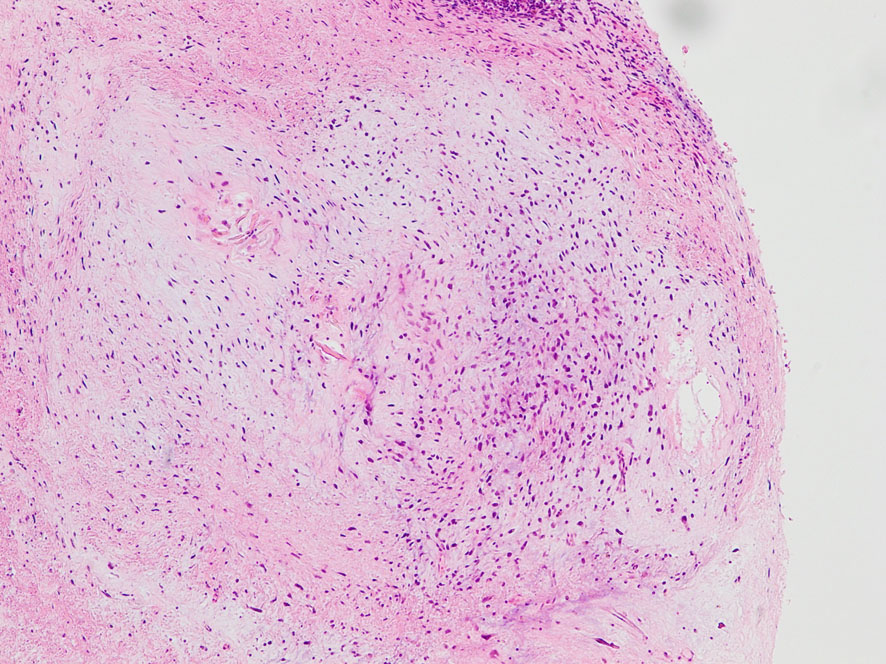

照射後の奇形腫の病理像

左上にはcartilage,右上にはkeratin squamous tissueがみられます。左下は繊維生組織のみdense collagenous tissueです。

生検術で胎児性癌と未熟奇形腫の混合型と診断されたために,化学療法と61.1グレイの放射線治療がなされていました。しかし,大きな松果体腫瘍が残り全摘出したものです。この子の腫瘍は治っていて元気に暮らせています。

奇形腫の照射後はいつもそうなのですが,dense collagenous tissueとfibroblastic spindle cellが組織の主体となっています。要するに肉芽腫のようなものです,ですから,手術摘出ではものすごく硬い線維性の腫瘍となっていてハサミでも切れずに難渋します。出血もしないし脳とは剥離できるのできます。放射線化学療法前の生検による組織像(悪性要素)は消失して単なる成熟奇形腫との病理診断となってしまいます。しかし,この組織のどこかに悪性度の高い細胞が潜んでいて,播種再発するなどということも経験しました。放射線治療後の病理組織診断はその後の予後の予想のためには役に立ちません。